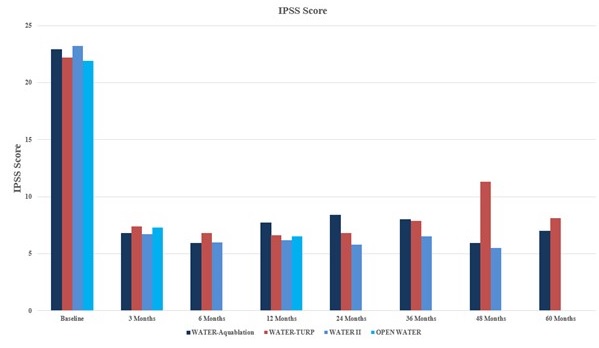

alternative resective procedures. In our U.S. pivotal trial, Waterjet Ablation Therapy for Endoscopic Resection of prostate tissue, or the WATER study, Aquablation therapy demonstrated superior safety and non-inferior efficacy results compared to transurethral resection of the prostate, or TURP, the historical standard of care for the surgical treatment of BPH. In the WATER and WATER II studies, surgical retreatment rates were only 5.2% at five years and 3.0% at four years, respectively. In the OPEN WATER study, there were no surgical retreatments at one year. The retreatment rates in the WATER and WATER II studies compare favorably to surgical retreatment rates observed for alternative treatments for BPH. One study published in the BJU International Journal reported on 52,748 men undergoing TURP or PVP with an approximated three-year freedom from surgical retreatment of 92% and 89%, respectively. A second study published in the Journal of Urology reported on 43,041 men undergoing TURP, PVP, enucleation, or open simple prostatectomy with an approximated three-year freedom from surgical retreatment of 93%, 89%, 94%, and 96%, respectively.

Clinical diagnosis of BPH typically involves a number of tests that are used to assess the degree of LUTS and determine whether the symptoms are caused by BPH or another condition. A symptom score index utilizes standardized questionnaires to quantify a patient’s degree of LUTS. One of the most common scoring systems is the International Prostate Symptom Score, or IPSS. Using this scoring system, LUTS are classified as either mild, moderate or severe. The IPSS questionnaire is a key tool used to evaluate treatment options and assess treatment success. Other commonly used tests include a digital rectal exam, urine sample tests, imaging scans, blood tests and uroflowmetry tests, which measure the strength and amount of urine flow during urination. Patients suffering from symptoms of BPH are typically first seen by a primary care physician, who may diagnose and manage the patient, or refer the patient to a urologist. A urologist is a physician who specializes in diseases of the urinary tract in both males and females as well as the male reproductive system. Urologists are trained to perform surgery for various types of urologic conditions, including BPH.

Resective Procedures. In resective surgery, tissue is removed during the procedure. Resective prostate procedures generally provide more significant and longer-lasting symptom relief than non-resective procedures, but may result in a higher incidence of irreversible complications, including urinary incontinence, erectile dysfunction and ejaculatory dysfunction. Resective procedures generally provide IPSS reduction of approximately 15 points. These procedures are typically performed in the hospital or outpatient surgery center under general or spinal anesthesia. In 2019, approximately 290,000 resective surgeries were performed in the United States, accounting for over 70% of all BPH surgeries.

Non-Resective Procedures. In non-resective procedures, prostate tissue is not removed at the time of surgery. By not removing tissue, symptom relief is generally less significant and durable compared to resective procedures. Non-resective procedures generally provide IPSS reduction of approximately ten points. The two most common commercially available non-resective procedures are prostatic urethral lift, or PUL, and water vapor therapy. PUL uses permanent implants of nitinol and stainless steel placed transurethrally to pin back and compress obstructing prostate tissue, thus creating a channel for improved urinary flow. Water vapor therapy utilizes principles of convection by transurethrally delivering water vapor into obstructing prostate tissue, which results in cell death and reduction of prostate volume over a period of three to six months. Non-resective procedures are generally approved for small- to average-sized prostates. In 2019, approximately 105,000 non-resective surgeries were performed in the United States.